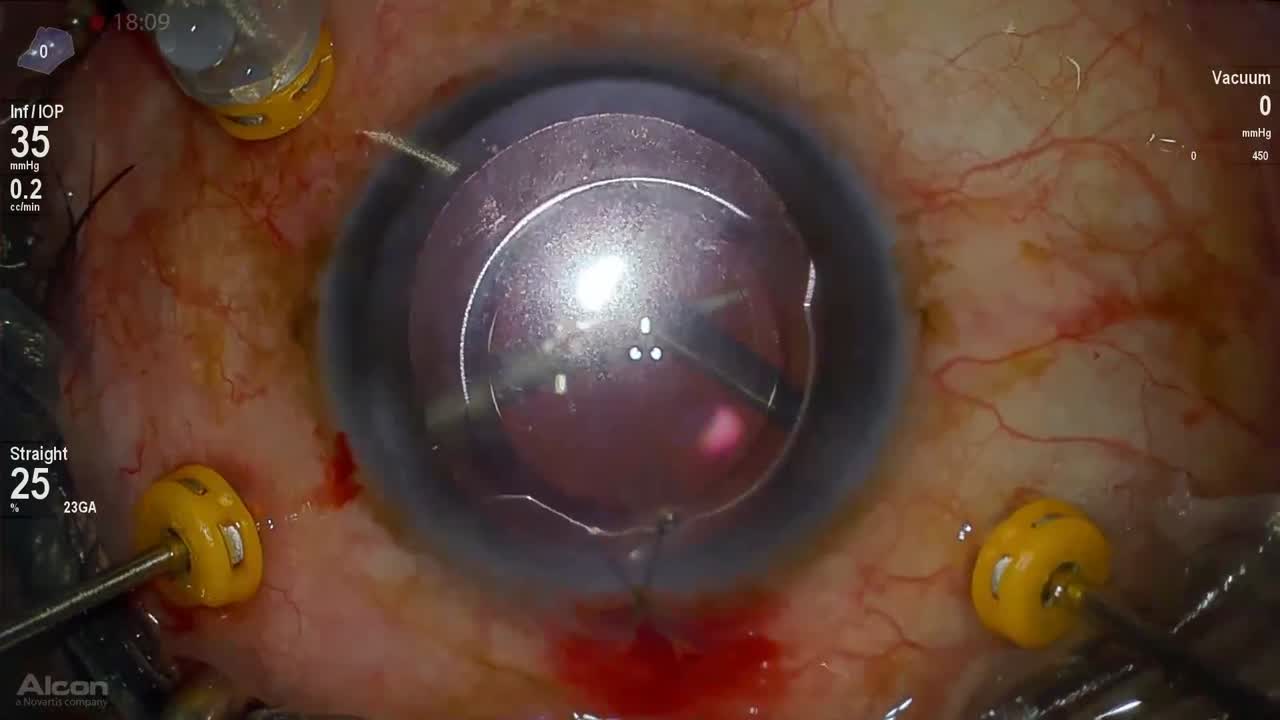

Dense Cataract

Anat Loewenstein, MD